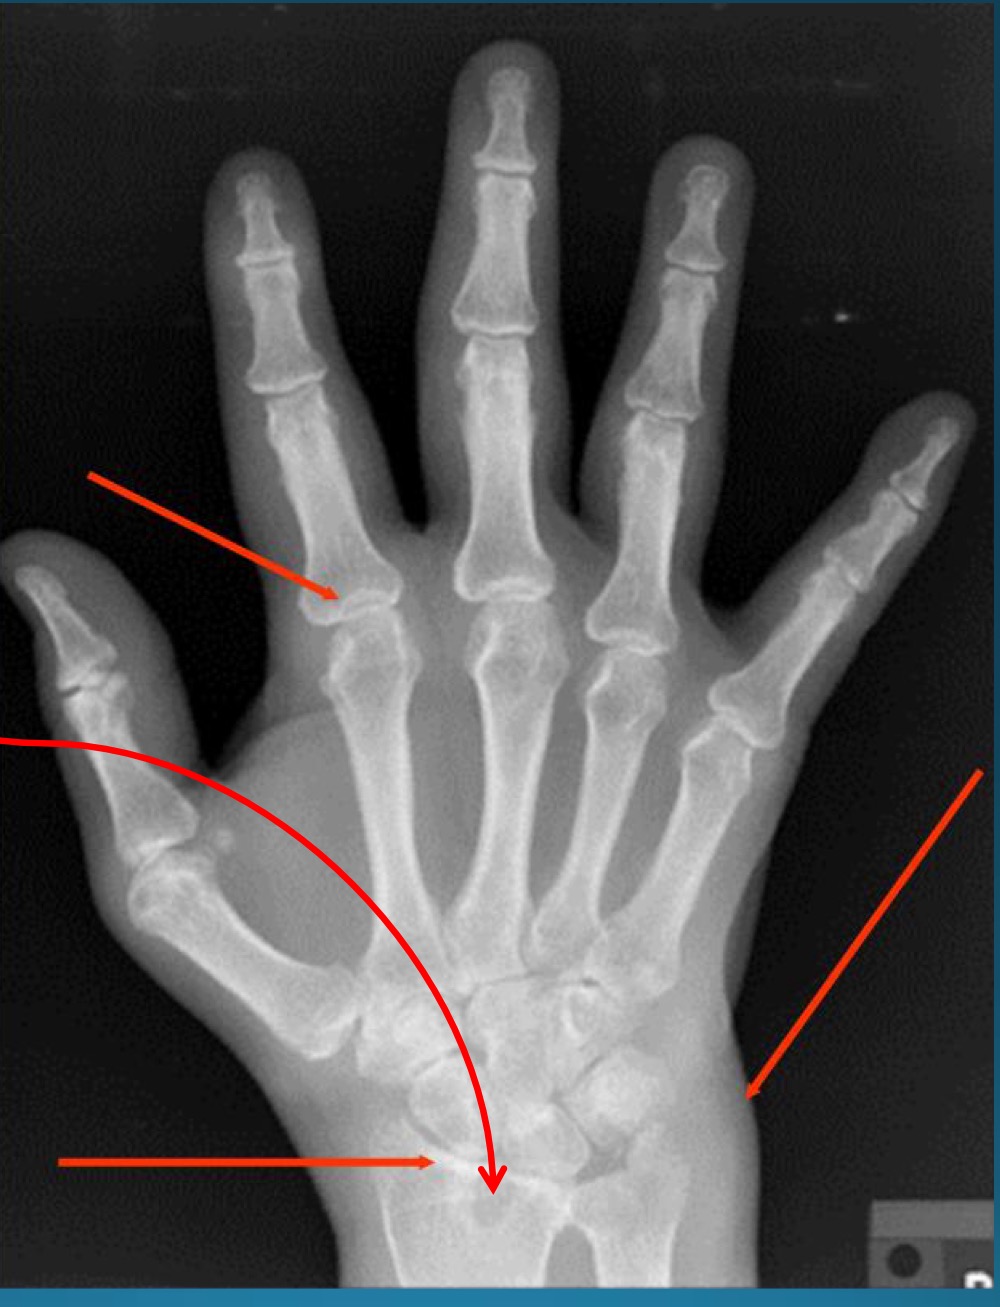

red arrows are pointing to what feature?

part of what diagnosis?

pseudocysts

RA

what are the target sites of RA

MCP and PIP

ulnar styloid

mid carpals

radiocarpal

2-3 metacarpal heads

marginal erosion due to RA are often located on what side of metacarpals

radial side